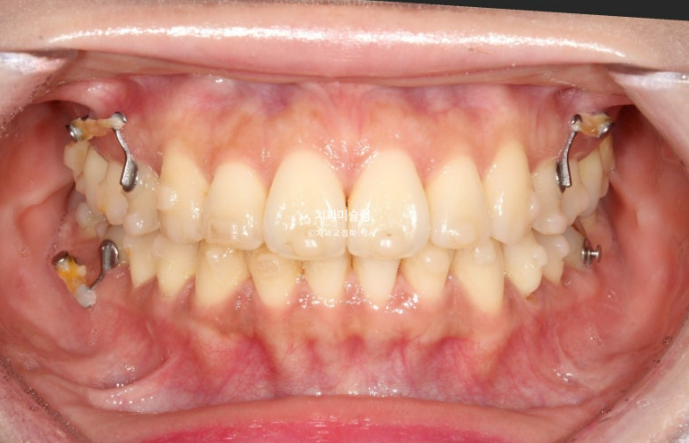

25년 5월에서 11월까지 23개 추가장치를 모두 낀 후 치료를 종료했습니다.

25.11

두번의 재제작을 통해 정확히 맞아진 중심선

어금니 교합은 물샐틈 없는 1급 교합관계를 보입니다.

이제 전후 비교 보겠습니다.

23.08~25.11

총 치료기간은 2년 3개월이고 재제작 2회입니다.

현재는 비베라를 매일 잘 때만 끼면서 결과 유지중입니다.